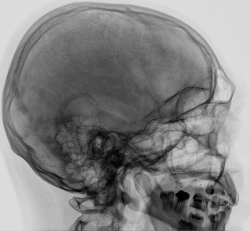

Рентгенография черепа в двух проекциях.

Справа - линейный перелом теменной кости с переходом на височную, и, вероятно на основание в СЧЯ

Перелом височной кости, преимущественно, в области чешуи, возможно, с переходом на теменную кость справа.

Линейный перелом височной и теменной костей,возможно с переходом на основание черепа.На счёт стороны поражения,желательно иметь вторую боковую проекцию,на стороне перелома линия просветления уже, предположу, что правая.

Косая линия перелома в проекции височно-затылочной области?

Справа над орбитой в лобной кости ≈ овальный участок разрежения костной структуры, довольно чётко очерченный; весьма возможно справа же в затылочной кости подобный, но меньшего размера участок. В носолобной проекции он виден выше первого.

Ага! Проворонил Петрович линейный перелом височной кости с переходом на теменную кость справа. Вот что значит практики травмы давно почти нет. Но зато теперь появилось подозрение на другой линейный перелом в височной обл., идущий горизонтально, пересекающий проекцию седла.

Пациент мне на голову свалился в 3 часа ночи, нейрохирург по всякому открещивался, что там нет ни чего, но с регламентом обследования при сотрясении головного мозга, конечно следует провести R-графию черепа. Но даже и после снимков черепа, он пытался списать всё на сосудистый рисунок, при этом указал, что у пациента пол года назад был хороший сотряс, лечился амбулаторно. Вообще если всю МСКТ-картину  суммировать, вообщем то,  как то он легко отделался, линейный перелом височной и теменной костей слева есть, там же на уровне височной доли хроническая субдуральная гематома, по краям перелома явно не свежий, но есть ещё и перелом в средней черепно-мозговой ямке, а именно дно турецкого седла. В левой лобной доле головного мозга имеется кистозно-глиозный участок, плотность на скане указана. С учетом отсутствие общей мозговой симптоматики, я так понял пациента отправили домой.

небольшая хроническая гематома